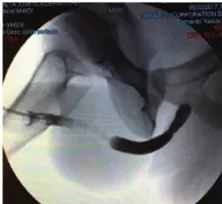

Απεικόνιση 1   Ουρηθρογραφία ασθενούς με στένωμα 1 εκ. στην περιοχή της βολβικής ουρήθρας: (a) πριν τη διαστολή του στενώματος και (b) 6 μήνες μετά τη διαστολή του στενώματος με το μπαλόνι Optilume.